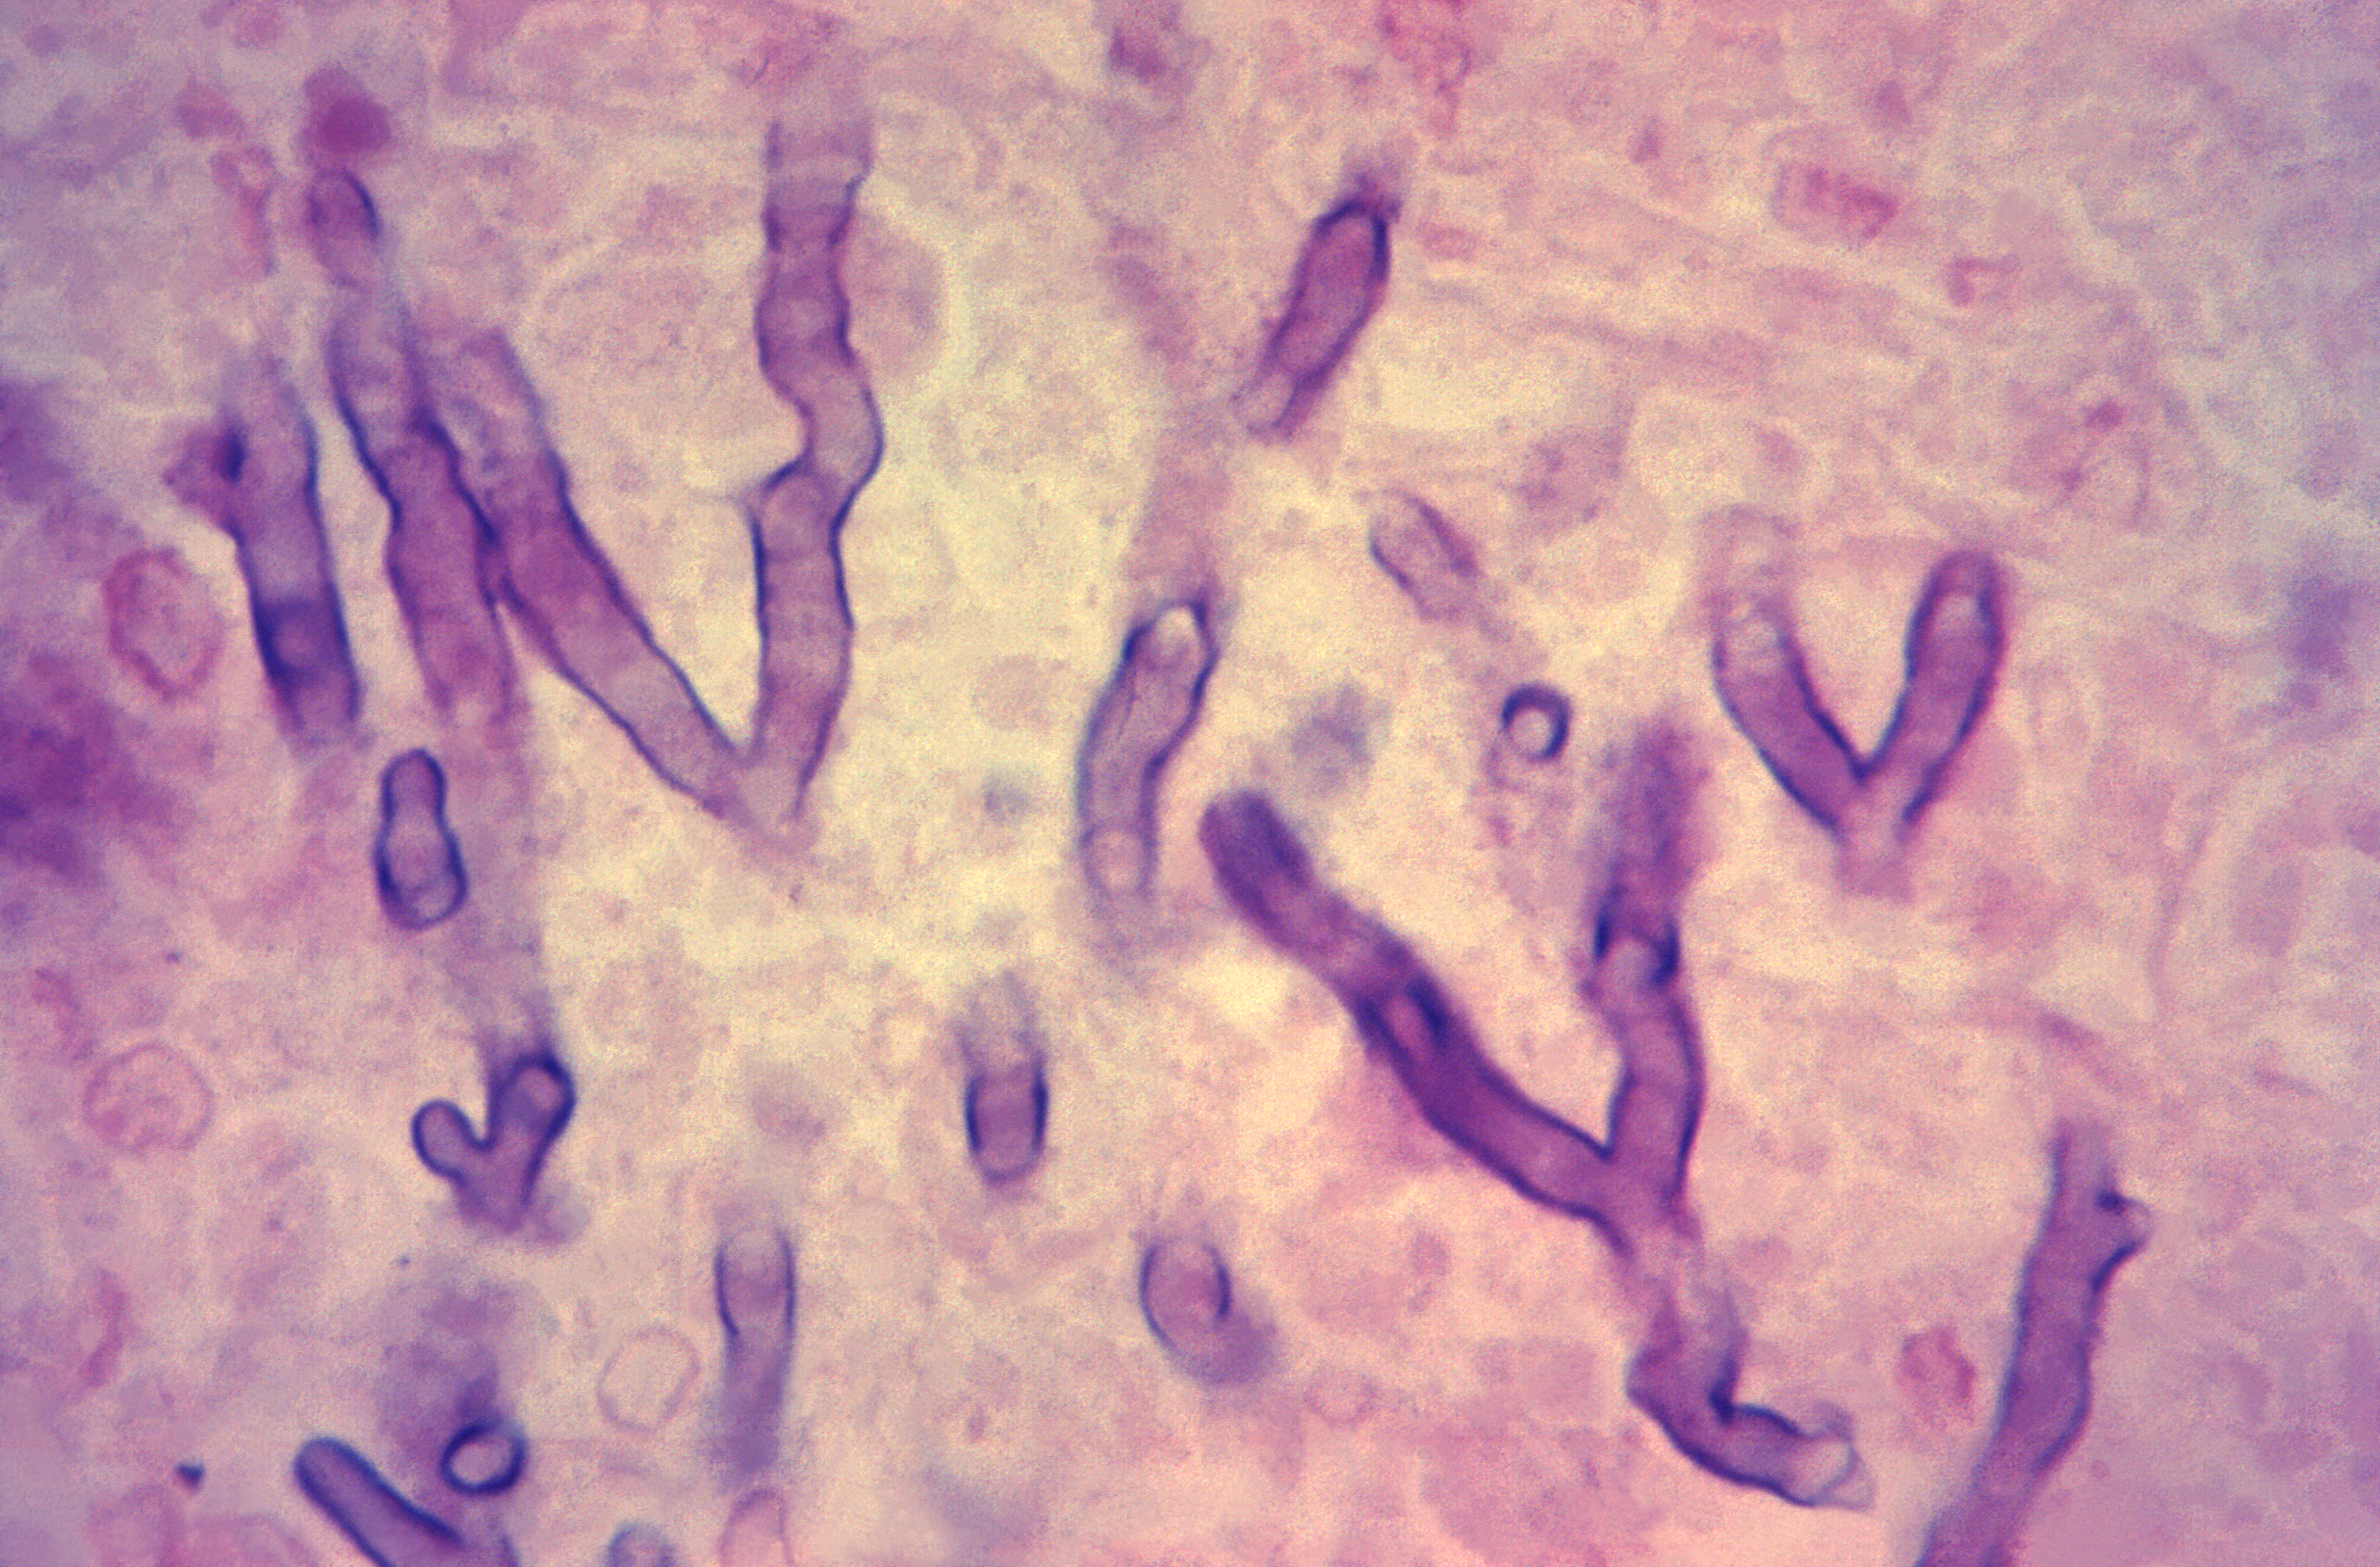

Daarnaast kunnen schimmelstructuren worden aangetoond met behulp van histopathologische kleuringen22,69. BAL en weefsels verkregen met biopsie zijn hiervoor de meest geschikte materialen. De standaard H&E (hematoxyline en eosine) kleuring wordt gebruikt om te bepalen of er sprake is van ontsteking, maar is niet specifiek voor schimmels. Desondanks kunnen hyfen en schimmels met deze kleuring wel worden opgemerkt. Bij vermoedens van een schimmelinfectie kan het nuttig zijn om aanvullend een PAS (Periodic Acid-Schiff) en een Grocott’s (Grocott-Gomori’s methenamine silver) kleuring uit te voeren. Hiermee worden schimmeldraden specifiek aangekleurd, waardoor deze beter zichtbaar zijn en gebruikt kunnen worden om schimmeldraden in weefsel te detecteren.

Een nadeel van microscopie is de beperkte gevoeligheid22,69. Met behulp van microscopie kunnen schimmeldraden worden aangetoond, maar betrouwbare identificatie van de schimmel is niet mogelijk. Als er gesegmenteerde schimmeldraden worden gezien met dichotome vertakkingen zou dit bij een Aspergillus infectie kunnen passen. Echter ook veel andere schimmels kunnen dezelfde kenmerken hebben. Bij infecties door Mucorales worden juist geen of weinig segmenten gezien in de schimmeldraden, zijn de draden erg wisselend van diameter en vertakken de schimmeldraden recht (op 90 graden) af.

Deze microscopiefoto van een met hematoxyline-eosine (H&E) gekleurd menselijk longweefselmonster, geoogst van een patiënt met pulmonale aspergillose, toont de histopathologische veranderingen door de aanwezigheid van Aspergillus sp. schimmelorganismen. Let op de vertakkende hyfen tussen het longweefsel.

Bron: CDC/ Armed Forces Institute of Pathology (AFIP); Dr. Hardin:

https://phil.cdc.gov/Details.aspx?pid=15630

Microscopiefoto van (hematoxyline-eosine (HE)-gekleurd menselijk longweefsel toont de aanwezigheid van myceliumschimmelfilamenten bij een patiënt met mucormycose (phycomycose), ook wel bekend als een vorm van zygomycose.

Bron: CDC/ Dr. Lucille K. Georg